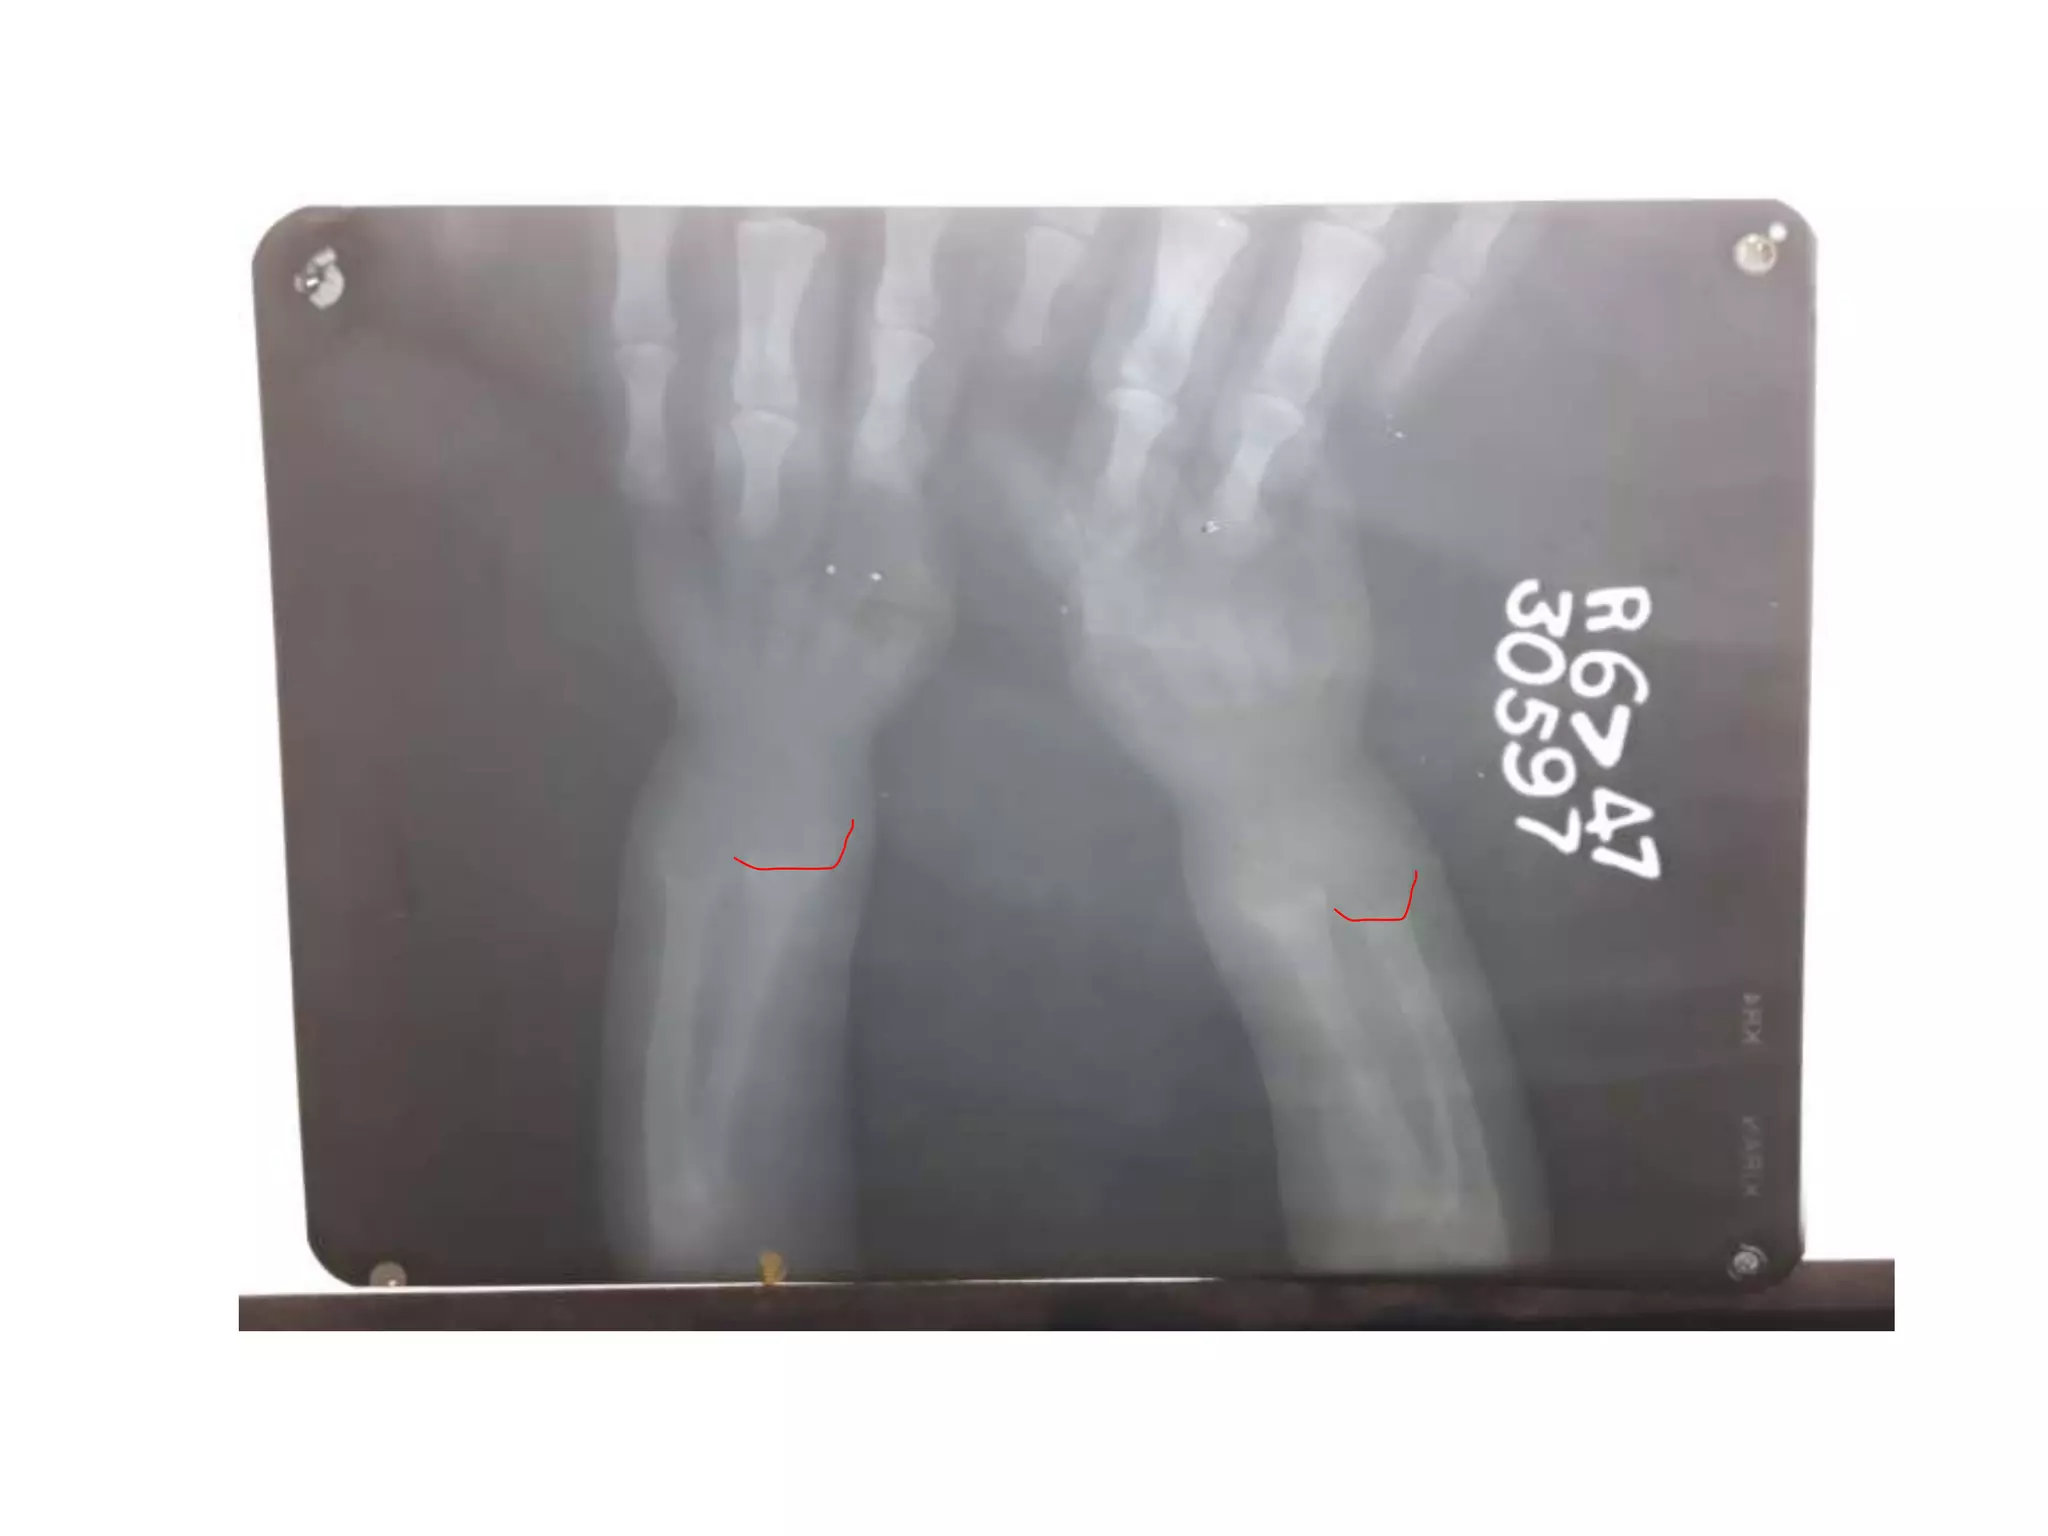

SCURVY

• Generalised osteopenia

• cortical thinning: “pencil-point” cortex

• Periosteal reaction due to subperiosteal

haemorrhage

• scorbutic rosary: expansion of the

costochondral junctionsmay relate to the

fracturing of the zone of provisional

calcification during normal respiration

• similar to the rachitic rosary appearance as

seen in rickets

• Haemarthrosis

• Wimberger ring sign: circular, opaque

radiologic shadow surrounding epiphyseal

centres of ossification, which may result

from bleeding

• Frankel line: dense zone of provisional

calcification

• Trümmerfeld zone: lucent metaphyseal band

underlying Frankel line

• Pelken spur: metaphyseal spurs which result

in cupping of the metaphysis

SCURVY • Generalised osteopenia •cortical thinning: “pencil-point” cortex • Periosteal reaction due to subperiosteal haemorrhage • scorbutic rosary: expansion of the costochondral junctionsmay relate to the fracturing of the zone of provisional calcification during normal respiration • similar to the rachitic rosary appearance as seen in rickets • Haemarthrosis • Wimberger ring sign: circular, opaque radiologic shadow surrounding epiphyseal centres of ossification, which may result from bleeding • Frankel line: dense zone of provisional calcification • Trümmerfeld zone: lucent metaphyseal band underlying Frankel line • Pelken spur: metaphyseal spurs which result in cupping of the metaphysis